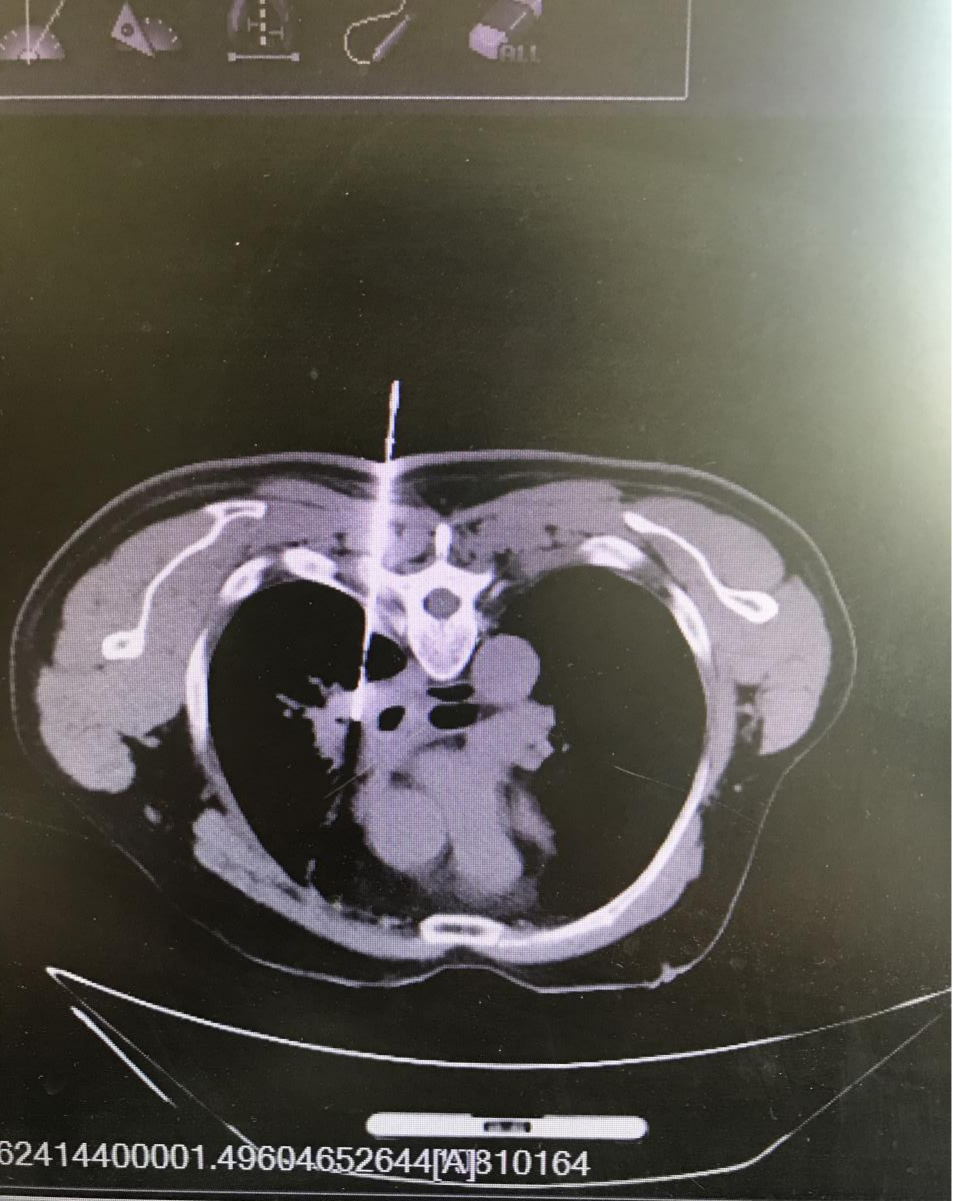

通过穿刺前设计进针路径,最终得到的是一条完美的组织条。通过组织条在病理专家的火眼金睛下,得到准确的结果,指导患者精确治疗。

齐医附属一院肿瘤内科自开展“同轴活检”技术以来,穿刺活检已超过500余例,技术成熟。它创伤性小,安全性高,准确率高达95%以上,尤其对于病灶较深的部位,例如肺部、腹腔(肝、胰、肾),CT引导下活检更具优势,操作简便、费用低廉、并发症少,能被大多数患者接受,不仅避免了患者疫情期间转诊就医的种种困难,还大大缩短了患者的住院时间。